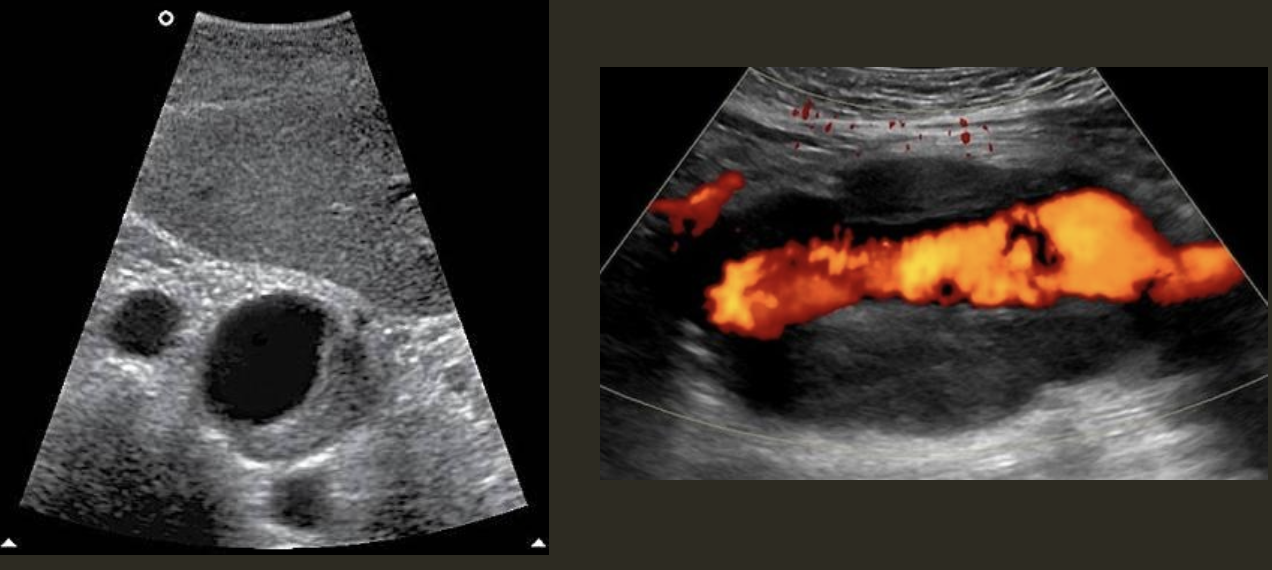

Pseudoaneurysm → rupture from intima layer contained in deeper layers of artery wall

2D US presentation: heterogenous, pulsating central structure with internal swirling of brighter echogenicity

color doppler: “yin-yang” sign, “to and fro” PW waveform

DDX: hematoma (hypoechoic intraluminal echoes, but not color flow or neck connecting), true aneurysm (wide rather than narrow neck continuous w/ artery, chronic rather than acute)